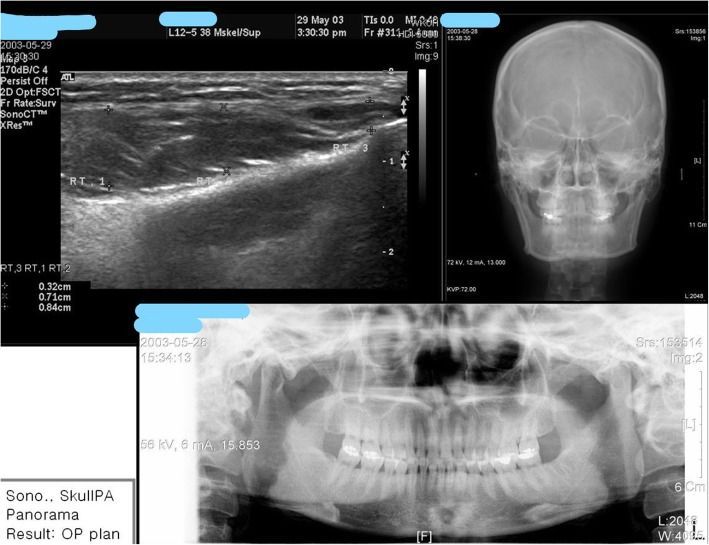

Trong các trường hợp quai hàm bạnh, vuông mà chúng tôi đã thực hiện, kế hoạch chỉnh sửa thường gồm ba phương pháp: chỉ tiêm botulinum toxin, kết hợp tiêm botulinum toxin và phẫu thuật cắt góc hàm hoặc chỉ phẫu thuật. Chúng tôi sẽ lập kế hoạch chỉnh sửa dựa trên ảnh siêu âm, X-quang sọ thẳng và X-quang toàn cảnh. Trong tổng số các trường hợp thì có đến 60% cần kết hợp cả tiêm botulinum toxin và phẫu thuật cắt góc hàm.

Quá trình chỉnh sửa được thực hiện dựa trên dạng hàm bạnh. Như đã nói ở trên, các dạng hàm bạnh được phân loại dựa trên nguyên nhân, do vấn đề về cơ, cấu trúc xương hay cả hai. Việc xác định dạng hàm bạnh hay nguyên nhân được thực hiện dựa trên ảnh X-quang toàn cảnh, X-quang sọ thẳng và siêu âm cơ (hình 13).

Loại I là hàm bạnh do phì đại cơ cắn và cấu trúc xương bình thường, góc hàm dưới nhô sang bên khi nhìn từ phía trước nhưng bình thường khi nhìn nghiêng (Hình. 14). Trong trường hợp này, chỉ cần tiêm botulinum toxin A mà không cần phải can thiệp phẫu thuật là đủ để có hiệu quả chỉnh sửa rất cao. Hình ảnh siêu âm cho thấy cơ cắn phì đại hơn 10mm trong khi ảnh X-quang toàn cảnh và sọ nghiêng không cho thấy độ nhô ra ngoài của góc hàm dưới. Điều này cũng được quan sát thấy trong những trường hợp mà góc hàm dưới nhô về phía sau. Phương pháp tiêm botulinum toxin phù hợp cho những trường hợp như vậy. Tuy nhiên, phương pháp tiêm botulinum toxin rất khó thay đổi quai hàm khi nhìn nghiêng nên có thể cân nhắc can thiệp phẫu thuật bổ sung.

Loại II là hàm bạnh do sự nhô ra của góc hàm dưới trong khi cơ cắn vẫn bình thường (hình 15). Những trường hợp này sẽ cần phẫu thuật cắt góc hàm và sau đó có thể tiêm botulinum toxin để cải thiện nốt. Sau phẫu thuật, khuôn mặt sẽ bị sưng phù, khiến bệnh nhân cảm thấy không khác gì so với lúc trước. Trong những trường hợp này thì có thể tiêm botulinum toxin A.

Loại III là hàm bạnh do cả phì đại cơ cắn và cấu trúc xương hàm dưới (quan sát thấy cả khi nhìn từ phía trước và nhìn nghiêng) (hình 16). Vấn đề này thường cần chỉnh sửa bằng cách phẫu thuật và tiêm botulinum toxin. Nếu chỉ tiêm botulinum toxin để làm gọn cơ thì khuôn mặt sẽ vẫn bị thô.